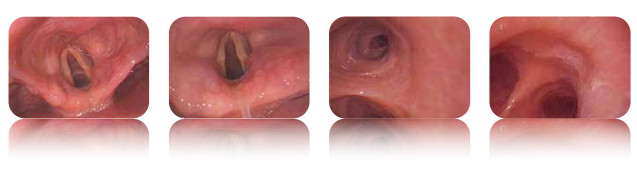

澳華可視喉鏡MBC-5是一款具有優(yōu)越性能和多功能設(shè)計(jì)的醫(yī)療設(shè)備。它采用了全新的圖像處理器成像技術(shù),能夠提供清晰、高清的圖像。這使得醫(yī)生能夠更準(zhǔn)確地觀察患者的喉部情況。

澳華可視喉鏡MBC-5在麻醉科、呼吸科、耳鼻喉科、ICU、急癥科和常日病房等領(lǐng)域具有廣泛的應(yīng)用前景。它能夠滿(mǎn)足不同領(lǐng)域醫(yī)生的需求,提供準(zhǔn)確的診斷和治療支持,為患者的健康保駕護(hù)航。